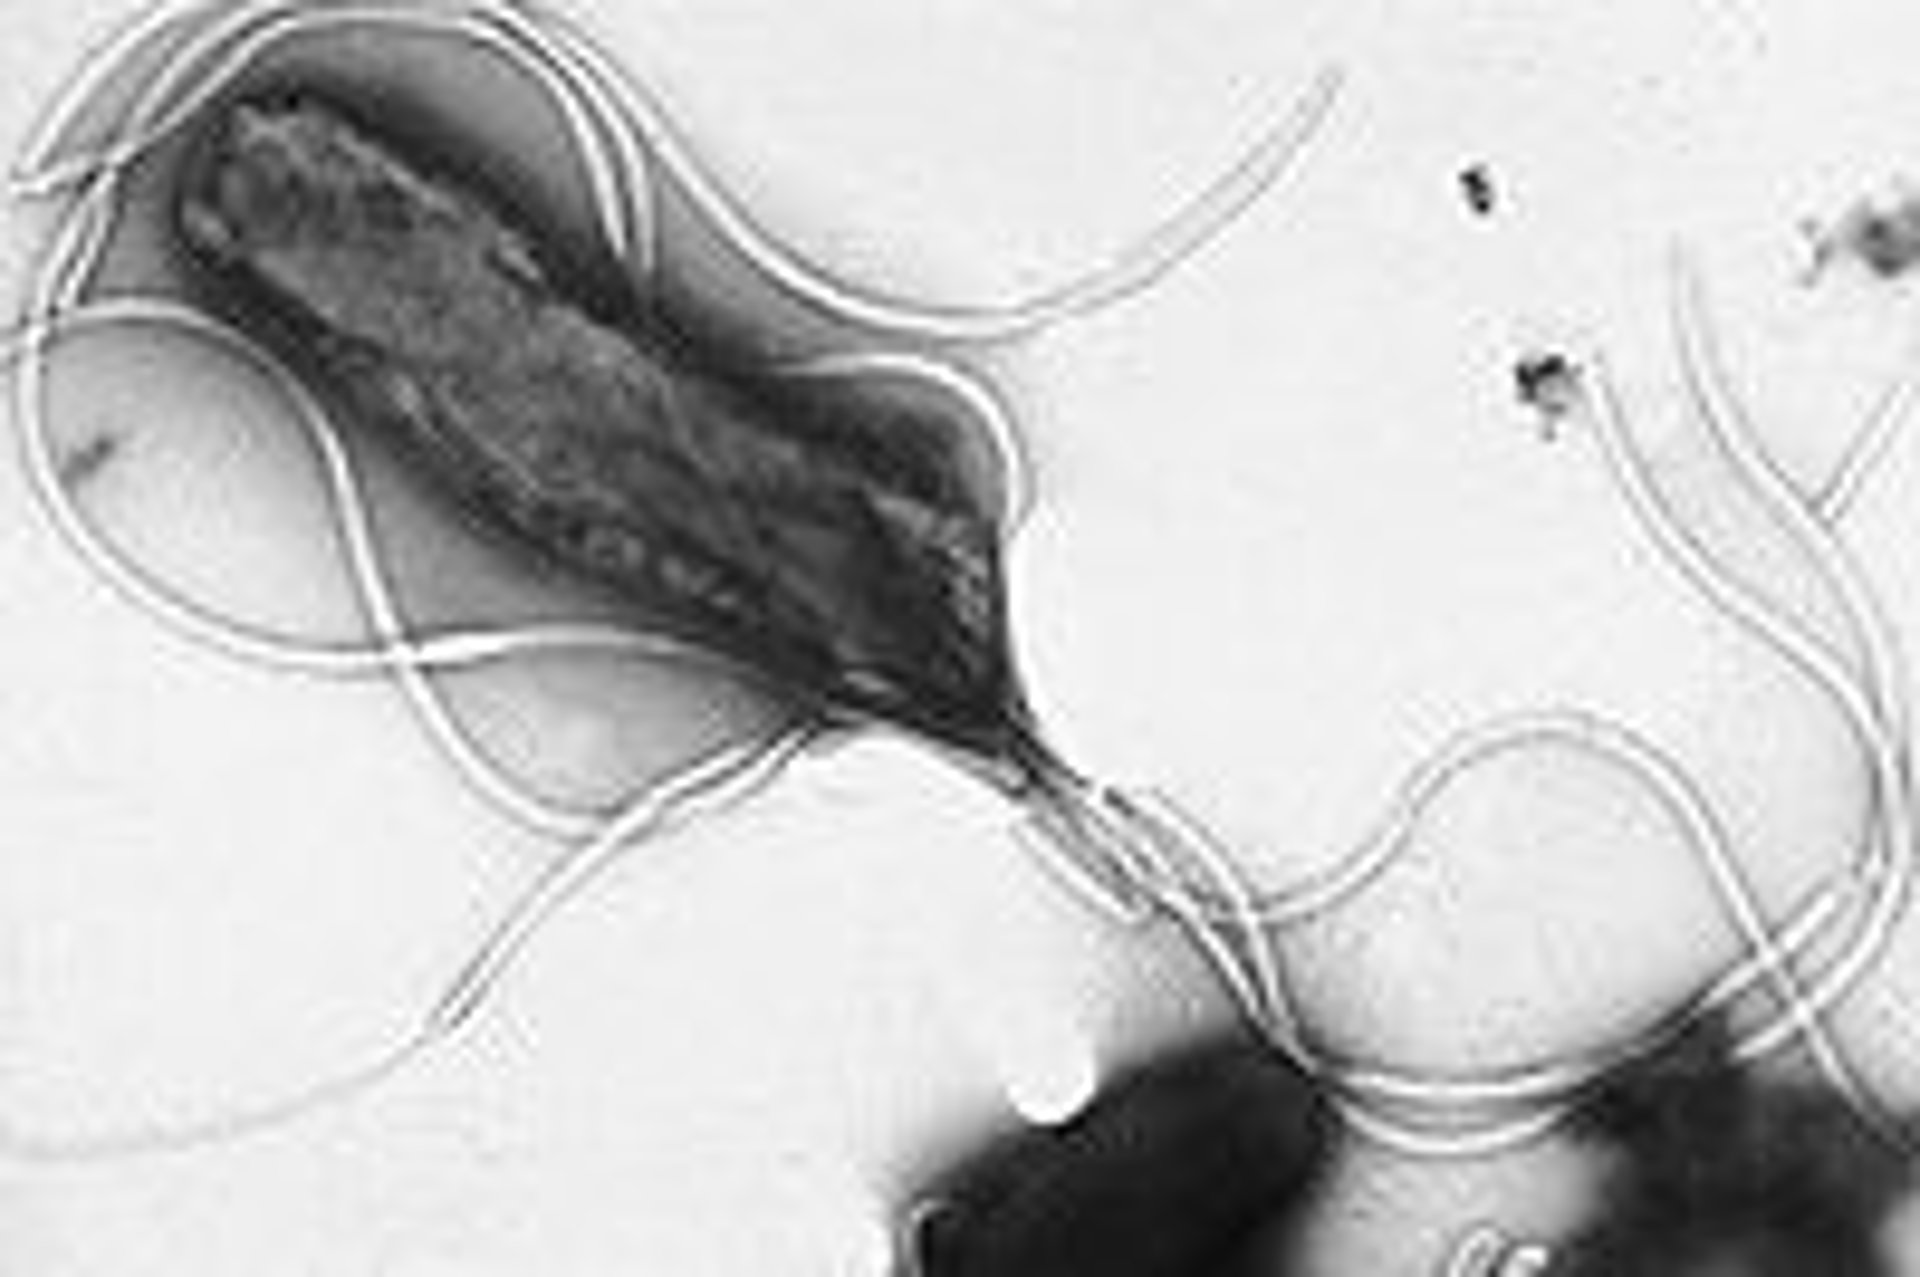

'Helicobacter pylori'

WIKIPEDIA

Investigadores del Instituto Catalán de Oncología (ICO) y del Instituto de Investigación Biomédica de Bellvitge (Idibell) han identificado a los pacientes con riesgo más elevado de sufrir un cáncer gástrico, provocado por la variante más agresiva de la bacteria 'Helicobacter pylori', que puede desencadenar un tumor tras 15 ó 25 años en el estómago.

En declaraciones a Europa Press, el jefe de la Unidad de Nutrición, Ambiente y Cáncer del ICO y responsable de los estudios, Carlos Alberto González Svatetz, ha constatado el descubrimiento de la cepa "más agresiva de la citada bacteria" y de que la presencia de una determinada lesión precancerígena en el estómago aumenta hasta 12 veces el riesgo de cáncer.

Cerca de un 80 por ciento de la población mundial sufre la infección por 'Helicobacter pylori' --entre un 50% y un 60% en España--, aunque la mayoría lo desconoce, hasta el 20 por ciento sufrirá una úlcera y un 1 o 2 por ciento desarrollará un cáncer gástrico, ha indicado el especialista.

Según González Svatetz, esta infección es "una de las más comunes en el mundo, y siempre ha estado en el estómago del ser humano por razones desconocidas", y también se desconocen los mecanismos de transmisión.

El proceso de aparición de un cáncer gástrico es lento, puede durar más de 20 años, y suele iniciarse con una infección pro la bacteria 'Helicobacter pylori' que produce una lesión.